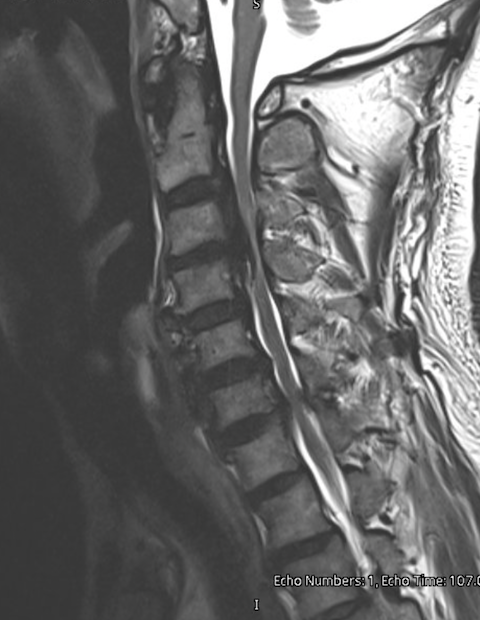

MRI scan of a human lumbar spine showing vertebrae, intervertebral discs, and spinal cord in black, white, and gray shades.

Posterior cervical decompression and fusion may be recommended when significant spinal cord or nerve compression occurs along with spinal instability.

Common conditions treated include:

• Cervical spinal stenosis

• Cervical myelopathy

• Multilevel cervical degenerative disease

• Cervical spine instability

• Certain cases of cervical deformity

Surgery may be recommended when symptoms affect walking, hand coordination, or overall neurologic function.